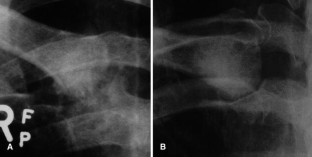

Fig. 4.